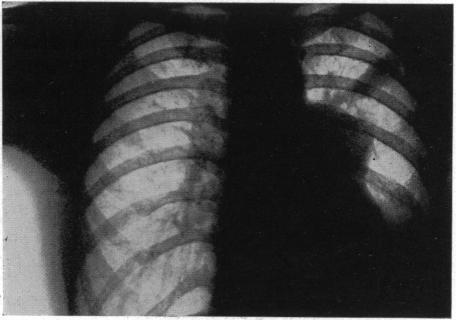

INTRATHORACIC DERMOIDS: WITH THE REPORT OF A CASE OF TOTAL EXTIRPATION AT ONE SITTING BY A NEW METHOD OF THORACOTOMY.

Ann Surg. 1928 Sep;88(3):607-32. doi: 10.1097/00000658-192809000-00030.